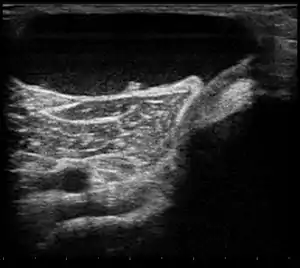

| Ultrasound image of Baker's cyst[2] | |

Diagnosis is by examination. A Baker's cyst is easier to see from behind with the patient standing with knees fully extended. It is most easily palpated (felt) with the knee partially flexed. Diagnosis is confirmed by ultrasonography, although if needed and there is no suspicion of a popliteal artery aneurysm then aspiration of synovial fluid from the cyst may be undertaken with care. An MRI image can reveal presence of a Baker's cyst.